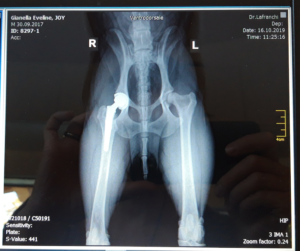

Joy è un incrocio di 1 anno e mezzo, con tantissimo amore da offrire a tutti, è il migliore compagno d’avventure di nostra figlia di tre anni e al momento sta facendo da papà a 7 gattini orfani. Poco più di un anno fa un annuncio ha attirato la nostra attenzione, un cucciolo di sei mesi cercava casa dopo un adozione andata male, presentava vari problemi dovuti allo stress e molte paure. È stato un colpo di fulmine per tutta la famiglia! Con tanto amore, pazienza, passeggiate adeguate, osteopatia e alimentazione adeguata ha ripreso un ottima forma fisica, ma purtroppo dalla displasia dell’anca (riconosciuta dalla nascita) non può guarire. Infatti da 3 mesi, a seguito di una probabile lussazione dell’anca dovuta dalla fragilità per la displasia, ha iniziato a zoppicare e provare forti dolori. Su consiglio del nostro veterinario (in attesa dell’intervento per la protesi dell’anca) per evitare che peggiori, doppiamo sempre tenerlo al guinzaglio e non può più giocare con gli altri cani o con noi. Inoltre, giornalmente dobbiamo somministrargli degli antidolorifici per riuscire almeno a fare le piccole passeggiate per i bisogni primari. Il costo dell’intervento ammonta a 4.500.- fr. ed è da fare al più presto per evitare complicazioni e dopo questa operazione potrà vivere una lunga vita felice ed agile come mai prima. Purtroppo non è facile per una giovane famiglia avere questa disponibilità e ci troviamo costretti a dover chiedere aiuto. È un cane fantastico e malgrado il forte dolore che prova, ed i suoi occhioni lo dicono chiaramente, continua ad essere dolce e gentile con tutti, portando gioia ed allegria in casa come un tempo. Grazie di cuore a tutti coloro che ci aiuteranno a finanziare questo intervento per far vivere a Joy una lunga vita felice!